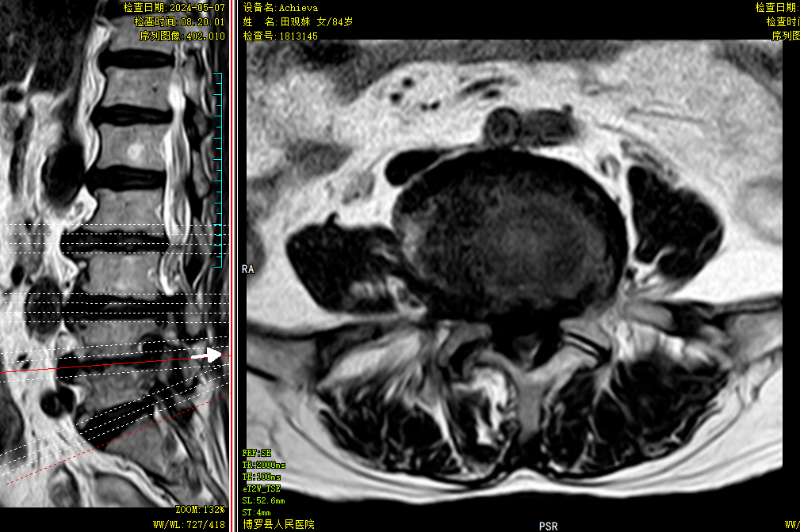

△術前MR可見腰3/4、腰4/5椎間盤突出,伴椎管狹窄嚴重、神經根受壓、馬尾神經冗余。